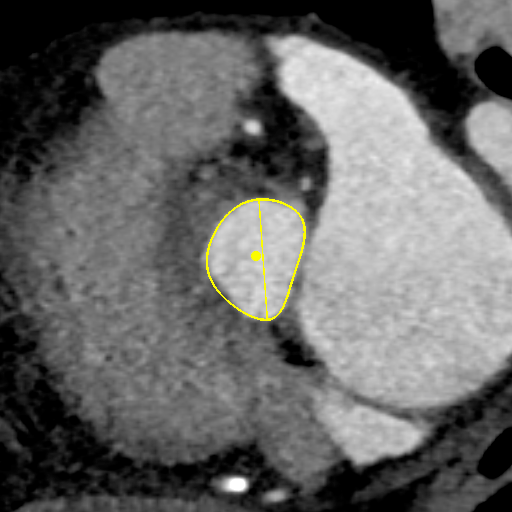

主动脉CT

主动脉瓣环平均直径:22.1mm;

左室流出道平均直径:23.7;

左冠脉开口:12.3mm;

右冠脉开口高度:11.2mm。

术前讨论:患者为三叶瓣主狭,左右冠瓣叶长,开口低,瓦氏窦小,左右冠高风险。

袁义强院长总结了该病例特点:三叶瓣,左右冠均高风险,解剖适合TAVR,年龄73岁,存在明确TAVR手术适应症。选择右股动脉入路,根据CT测量分析选择瓣膜大小,窦部情况可,瓣环平均直径22.1mm,计划22号球囊预扩,评估冠脉风险,选择植入24mm瓣膜。